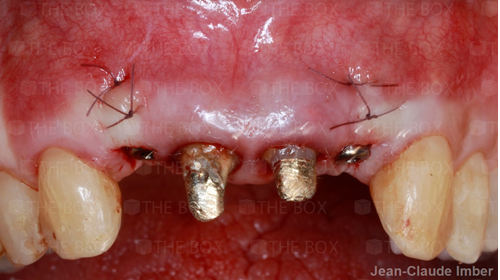

A new case was made public by Jean-Claude Imber check it out here.